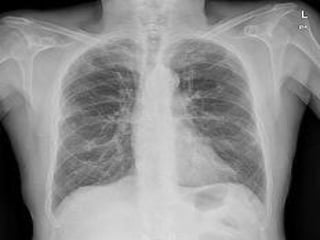

Este estudio descriptivo transversal analizó las enfermedades más frecuentes que requieren cuidados paliativos en Atención Primaria. La muestra consistió en 43 pacientes en un centro de salud urbano en 2011. Los resultados mostraron que el 51% de los pacientes eran hombres y el 49% eran mujeres. Las enfermedades más comunes que requirieron cuidados paliativos en hombres fueron cáncer de próstata, cáncer colorrectal y cáncer gástrico, mientras que en las mujeres fueron cáncer de mama